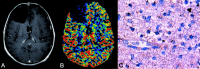

Background and purpose: Relative cerebral blood volume (rCBV) measurements derived from perfusion-weighted imaging (PWI) may be useful to evaluate angiogenesis and preoperatively estimate the grade of a glioma. We hypothesized that rCBV is correlated with vascular endothelial growth factor (VEGF) expression as marker of the angiogenic stimulus in presumed supratentorial low-grade gliomas (LGGs).

Methods: From February 2001 to February 2004, we examined 20 adults (16 men, four women; mean age 36 years; range, 23-60 years) with suspected (nonenhancing) supratentorial LGG on conventional MR imaging. Preoperative MR imaging used a dynamic first-pass gadolinium-enhanced, spin-echo echo-planar PWI. In heterogeneous tumors, we performed stereotactic biopsy in the high-perfusion areas before surgical resection. Semiquantitative grading of VEGF immunoreactivity was applied.

Results: Nine patients had diffuse astrocytomas (World Health Organization grade II), and 11 had other LGG and anaplastic gliomas. In patients with heterogeneous tumors on PWI, the high-rCBV focus had areas of oligodendroglioma or anaplastic astrocytoma on stereotactic biopsy, whereas the surgical specimens were predominantly astrocytomas. Anaplastic gliomas had high rCBV ratios and positive VEGF immunoreactivity. Diffuse astrocytomas had negative VEGF expression and mean rCBV values significantly lower than those of the other two groups. Three diffuse astrocytomas had positive VEGF immunoreactivity and high rCBV values.

Conclusion: Our results confirmed the correlation among rCBV measurements, VEGF expression, and histopathologic grade in nonenhancing gliomas. PWI may add useful data to the preoperative assessment of nonenhancing gliomas. Its contribution in predicting tumor behavior and patient prognosis remains to be determined.